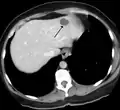

A liver hemangioma as seen on CT

Infantile haemangiomas in the liver are found in 16% of all liver haemangiomas. Its sizes are usually less than 1 to 2 cm in diameter. It may show a "flash-filling" phenomenon in which there is the fast enhancement of the contrast material in the lesion instead of slow, centripetal, nodular filling of the lesions in usual hemangiomas. On CT and MRI, it shows rapid filling during arterial phase, with contrast retention in venous and delayed phases.[36]